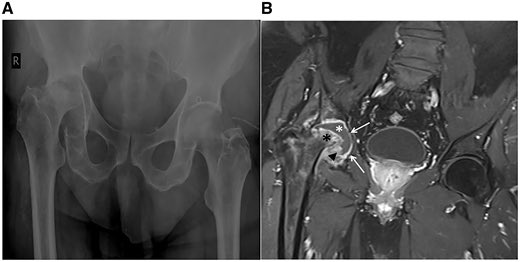

A 56yr old livestock farmer in Greece presents with 6 months of hip pain. No fever. Mild CRP elevation. Image below. Check here for the diagnosis: http://bit.ly/2JDmnLE

#casereports pic.twitter.com/dF3z3wN0sc